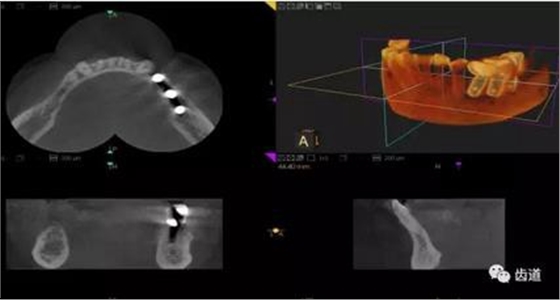

三)種植修復(fù)

CBCT在牙種植修復(fù)中的應(yīng)用。種植前利用CBCT對(duì)患者的牙床進(jìn)行檢查,可精準(zhǔn)判斷牙槽骨的寬度、厚度及高度、骨的密度、重要的顏面神經(jīng)、血管和鼻竇位置等。臨床醫(yī)生不僅可以在計(jì)算機(jī)直觀的看到牙槽骨的立體影像,還可以切換不同的視角來(lái)觀察硬組織之間的位置關(guān)系,在手術(shù)方案中避開危險(xiǎn)區(qū)域,保證手術(shù)的安全性。臨床醫(yī)生還可以利用CT數(shù)據(jù)進(jìn)行數(shù)字模型重建,配合軟件預(yù)先做好手術(shù)模板,使種植手術(shù)更安全快捷,避免在種植手術(shù)過(guò)程中不慎破壞神經(jīng)、鼻竇等解剖結(jié)構(gòu),導(dǎo)致顏面神經(jīng)麻痹、鼻竇炎等并發(fā)癥的發(fā)生。

1、下頜骨種植牙前測(cè)量準(zhǔn)備影像

2、上頜骨種植牙前準(zhǔn)備影像

3、下頜骨種植牙術(shù)后